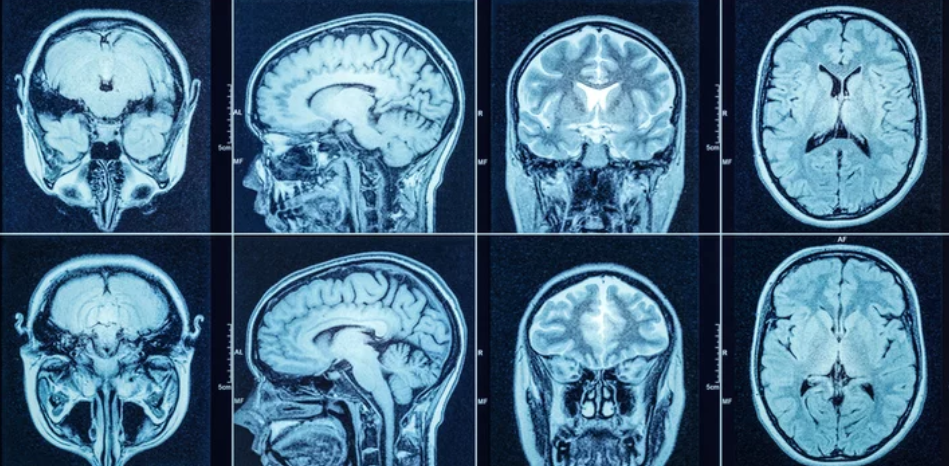

Neurology: Advanced Brain Mapping and Functional Imaging

In neurology, MRI — especially functional MRI (fMRI) — is opening up new possibilities for understanding the human brain. By mapping neural activity and blood flow, fMRI is helping neurologists:

- Diagnose neurodegenerative diseases like Alzheimer’s and Parkinson’s

- Monitor brain activity in epilepsy and traumatic brain injuries

- Plan complex brain surgeries with precision

Emerging technologies, such as diffusion tensor imaging (DTI), are also being integrated into neurological departments to study brain connectivity and white matter integrity.